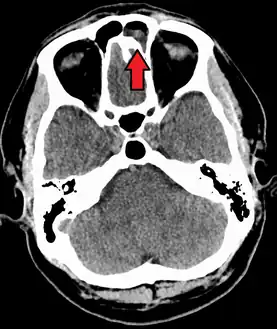

The proximity of the brain to the sinuses makes the most dangerous complication of sinusitis, particularly involving the frontal and sphenoid sinuses, infection of the brain by the invasion of anaerobic bacteria through the bones or blood vessels. Abscesses, meningitis, and other life-threatening conditions may result. In extreme cases, the patient may experience mild personality changes, headache, altered consciousness, visual problems, seizures, coma, and possibly death.[16]

Sinus infection can spread through anastomosing veins or by direct extension to close structures. Orbital complications were categorized by Chandler et al. into five stages according to their severity (see table).[25] Contiguous spread to the orbit may result in periorbital cellulitis, subperiosteal abscess, orbital cellulitis, and abscess. Orbital cellulitis can complicate acute ethmoiditis if anterior and posterior ethmoidal veins thrombophlebitis enables the spread of the infection to the lateral or orbital side of the ethmoid labyrinth. Sinusitis may extend to the central nervous system, where it may cause cavernous sinus thrombosis, retrograde meningitis, and epidural, subdural, and brain abscesses.[26] Orbital symptoms frequently precede intracranial spread of the infection . Other complications include sinobronchitis, maxillary osteomyelitis, and frontal bone osteomyelitis.[27][28][29][30] Osteomyelitis of the frontal bone often originates from a spreading thrombophlebitis. A periostitis of the frontal sinus causes an osteitis and a periostitis of the outer membrane, which produces a tender, puffy swelling of the forehead.

The diagnosis of these complications can be assisted by noting local tenderness and dull pain, and can be confirmed by CT and nuclear isotope scanning. The most common microbial causes are anaerobic bacteria and S. aureus. Treatment includes performing surgical drainage and administration of antimicrobial therapy. Surgical debridement is rarely required after an extended course of parenteral antimicrobial therapy.[31] Chronic sinus infections may lead to mouth breathing, which can result in mouth dryness and an increased risk of gingivitis. Decongestants may also cause mouth dryness.[32]